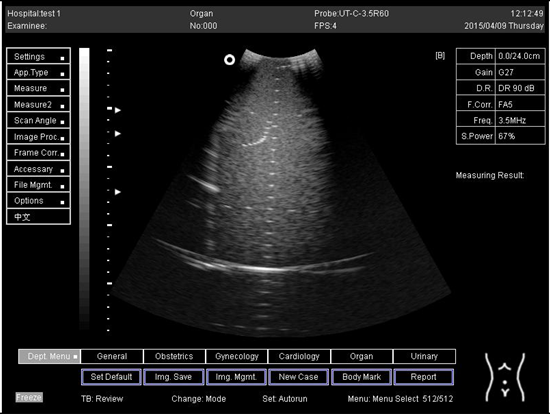

Table A5. The image taken for focal zone determination in different depth for curve probe.

Depth (cm)Diagram

24.0Biomimetics 07 00130 i034